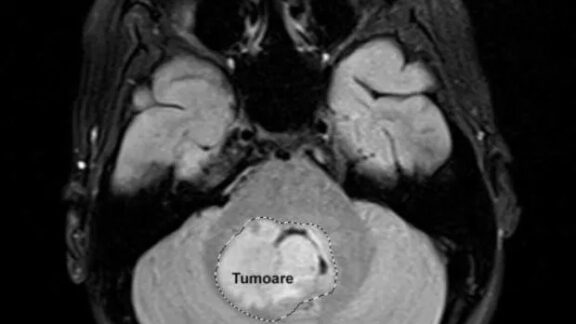

Tumoare la creier

Fetiţă diagnosticată cu tumoare pe creier salvată de la moarte